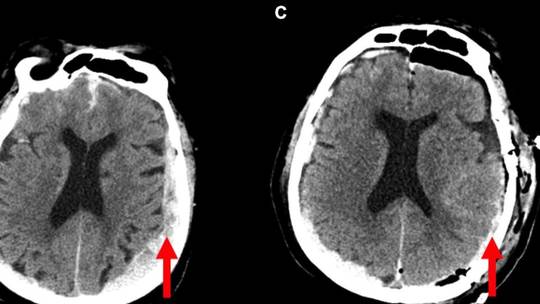

For the first time ever, scientists have recorded the activity of a dying human brain, discovering that it showed the same patterns as seen during dreaming, memory recall and meditation, a new study has revealed.